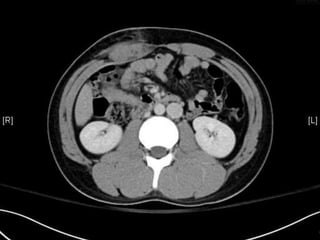

• CT:

 Shanmuganathan(2004)

 Sen:97%, spe:98%, accuracy:98% in penetrating stab wds

 Velmahos(2005)

 GSW: Sen 90.5, Spe: 96%

Radiology 2004:231:775-784

J trauma 2005:59:1155-1161